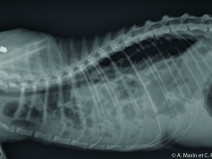

• Travaux pratiques de radiographie / Le Thorax

Le GEIM vous propose une séance de travaux pratiques de radiographies sur le thorax. Tous les aspects sont abordés sous la forme de TP de lecture de radiographies numériques sur station de travail Osirix sur Mac (3 vétérinaires maximum/ordinateur).